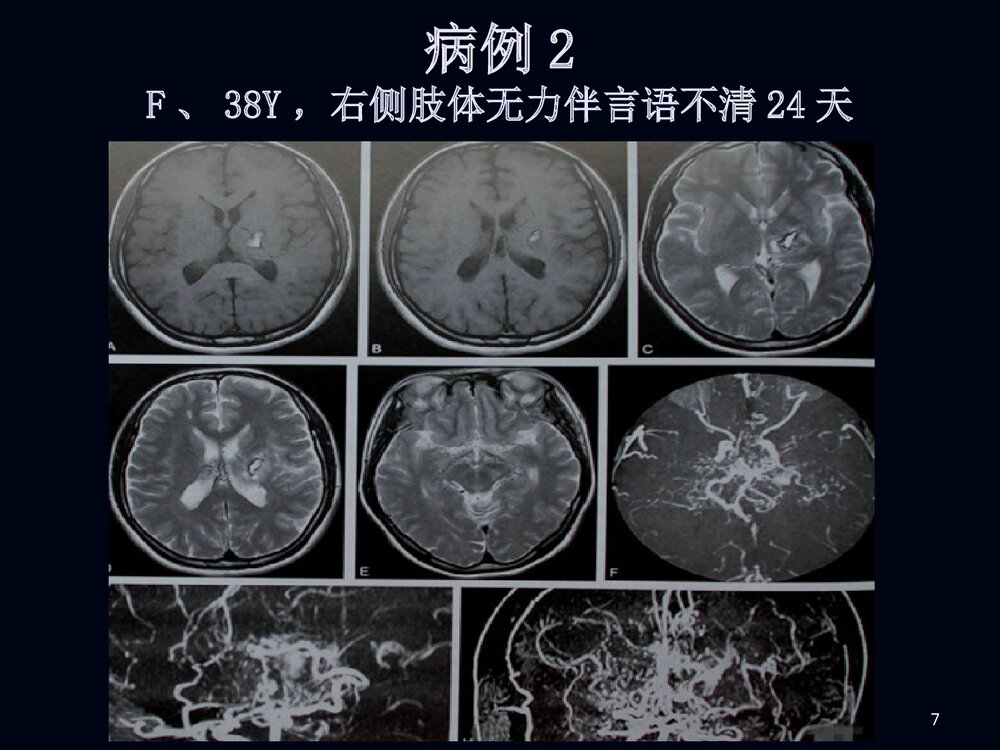

1烟雾病临床和影像诊断烟雾病临床和影像诊断2男性,男性,2020岁突发剧烈头痛岁突发剧烈头痛11小小时时3脑室穿刺脑室穿刺引流后增引流后增强强CTCT4MRIMRI5MRAMRA67病例病例22F、38Y,右侧肢体无力伴言语不清24天8MRIMRI910病例1DSA11烟雾病烟雾病病例2脑底异常血管网1213烟雾病烟雾病概述概述病理病理分型、分期分型、分期临床表现临床表现影像表现影像表现诊断诊断鉴别诊断鉴别诊断治疗治疗14概述概述烟雾病是以颈内动脉虹吸部或大脑前、中烟雾病是以颈内动脉虹吸部或大脑前、中动脉起始部缓慢的进行性的自发性狭窄或闭塞、动脉起始部缓慢的进行性的自发性狭窄或闭塞、并在脑底出现异常的小血管网为特点的一种脑血并在脑底出现异常的小血管网为特点的一种脑血管病。管病。在脑血管造影时,脑底...